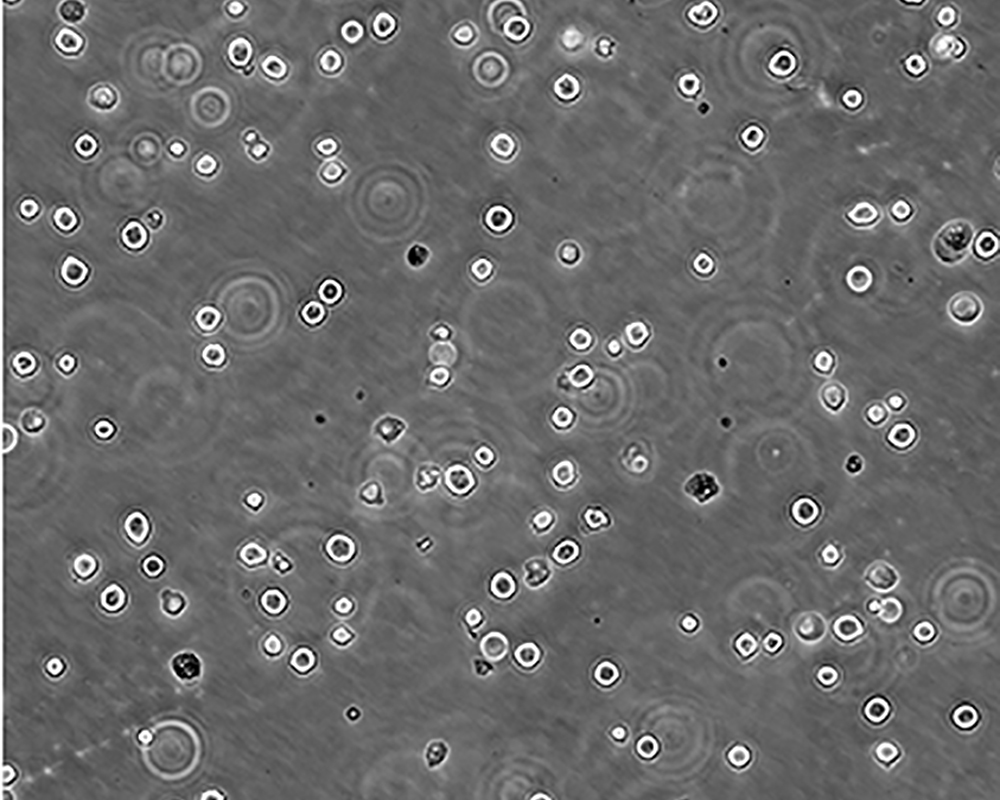

產品名稱 K-562 [K562]細胞

中文名稱 人慢性髓原白血病細胞

組織來源 慢性髓細胞白血病;女性

生長特性 suspension

培養基 IMDM+10% FBS+1% P/S

形態特征 lymphoblast

傳代方法 1:2-1:4

細胞描述 The cell population has been characterized as highly undifferentiated and of the granulocytic series. Studies conducted by Anderson, et al. , on the surface membrane properties led to the conclusion that the K-562 was a human erythroleukemia line. K-562 blasts are multipotential, hematopoietic malignant cells that spontaneously differentiate into recognizable progenitors of the erythrocytic, granulocytic and monocytic series. The effect of inducers on sublines derived from the original K-562 cell line have been reviewed by Koeffler and Golde. Karyological studies on various K- 562 sublines have been classified into three groups(A,B,C) by Dimery, et al. The strain obtained by the ATCC most closely resembles the B population. Occurrence of the Philadelphia chromosome, however, was of much lower frequency; none detected in 15 metaphases examined. The line is EBNA negative.

細胞凍存 Freeze medium: 50% basal medium+40% FBS+10%.DMSOStorage temperature: liquid nitrogen vapor phase

細胞運輸 干冰運輸(2ml凍存管)或活細胞運輸(T25細胞瓶)